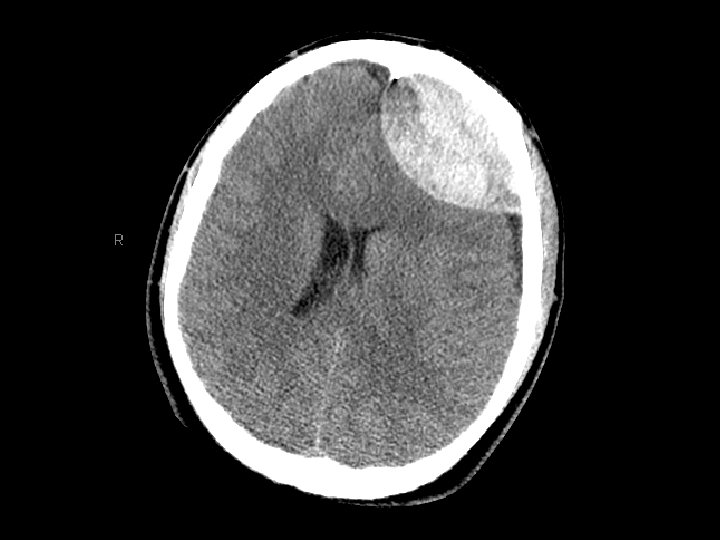

Epidural Hematoma (EDH) • Hemorrhage “above” the dura – Usually arterial (middle meningeal artery) but can also be from venous bleeding • CT: convex (lens shaped) area of blood – Bleeding restricted by the dura’s attachment to the skull • 5 -15% of patients with TBI on CT have an EDH

Epidural Hematoma (EDH) • Potentially rapidly expanding with mass effect and uncal herniation (fixed/dilated pupil) – “Awake and then die” • Most EDHs can be observed • EDHs with mass effect require surgical drainage